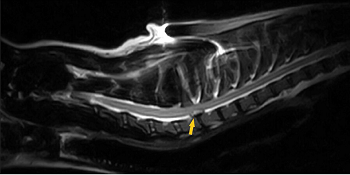

Cavalier with extruded disc in its neck is healed without

surgery.

In

a

February 2024 case study, two UK clinicians (Michelle du Toit

[right], Neringa Alisauskaite) report a 4-year-old cavalier King

Charles spaniel diagnosed with a painful condition due to a disc

extruding from his spine, in a case of

intervertebral disc

extrusion (IVDE) in the neck (cervical) region of the spine (at

C7-T1). The dog's symptoms included hyperesthesia (extreme pain and

sensitivity), a stiff gait, low head carriage, and reluctance to turn

the neck or lift the head. This condition was distinguished from

degenerative intervertebral disc disease (IVDD) in that it is not

considered to be degenerative. MRI was performed, and extruded disc

material was observed at the C7-T1 location on the spine, resulting in

50% reduction in the area of the vertebral canal and severe compression

of the spinal cord. The disc material also was compressing the C8 nerve

roots. (See MRI image below.) Surgical decompression was an

option, but the owner chose a more conservative therapy consisting of

exercise restriction and medication for a period of 4 to 8 weeks.

Initially, the dog was hospitalized for 8 days, followed by being

confined to his cage with only brief walks on leads.

Treatment

consisted of physical therapy and medication (gabapentin, amantadine,

paracetamol, and only when necessary, either methadone or

buprenorphine). The cavalier had a couple of relapses of extreme pain

and sensitivity and subsequently displayed right rear leg lameness. MRI

after 4 months showed another disc extruding at L5-L6, diagnosed as

degenerative IVDE (called "foraminal"), requiring surgery. However, the

MRI showed that the C7-T1 disc had returned to its proper position.